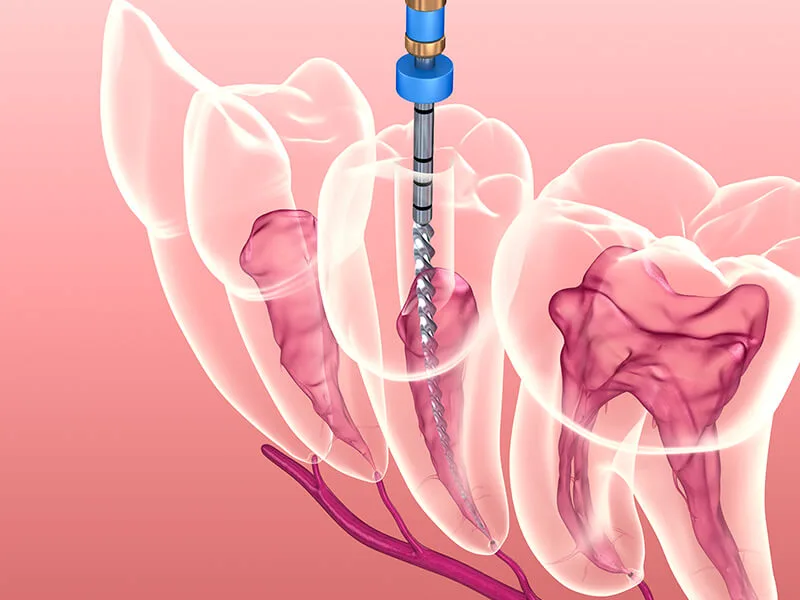

O consultório endodontia oferece uma série de benefícios cruciais para a longevidade da saúde dental. Este espaço é especializado em tratar problemas que afetam a polpa dentária, sendo a solução definitiva para quem sofre com dores intensas e quadros infecciosos.

Buscar o suporte de um consultório endodontia permite que o paciente elimine focos bacterianos de forma precisa. Através de técnicas modernas, a saúde bucal geral é aprimorada, estabelecendo um ambiente biológico muito mais saudável e protegido.

Um dos principais ganhos ao buscar o atendimento especializado é o alívio célere da dor. Pacientes que enfrentam quadros agudos encontram amparo imediato através de procedimentos que removem a polpa infectada, eliminando a fonte do sofrimento:

O tratamento endodôntico contribui para uma mastigação mais eficiente e segura. Ao salvar o dente, o especialista assegura que as forças oclusais permaneçam distribuídas, prevenindo desgastes irregulares e problemas na articulação da mandíbula.

Tecnologia de Precisão: Uso de microscopia operatória e localizadores apicais para maior exatidão;

O uso de equipamentos modernos resulta em intervenções menos invasivas e diagnósticos milimétricos. Na unidade técnica, o atendimento personalizado é prioridade, permitindo que todas as preocupações do paciente sejam acolhidas adequadamente.